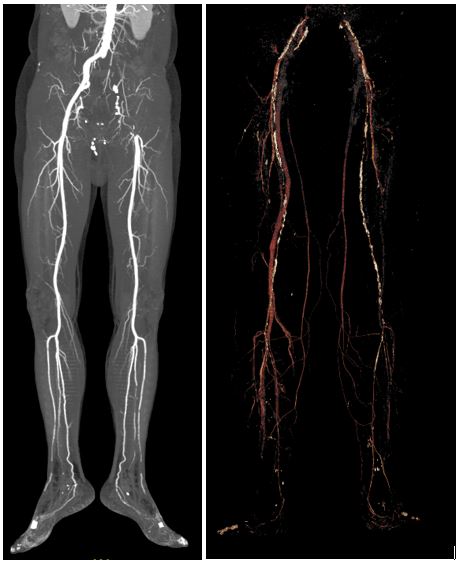

Детальная визуализация всех артерий от полости таза до стопы

КТ-ангиография артерий нижних конечностей — метод обследования, при котором компьютерную томографию с контрастированием выполняют для визуализации крупных и мелких артерий нижних конечностей. Эта методика визуализации позволяет оценить просвет, стенку сосудов, выявить наличие стенозов, окклюзий, аневризм, коллатерального кровотока и особенности анатомии сосудистого русла.

• Детальная визуализация всех артерий от полости таза до стопы.

КТ-ангиография с атеросклеротическим поражением сосудов нижних конечностей